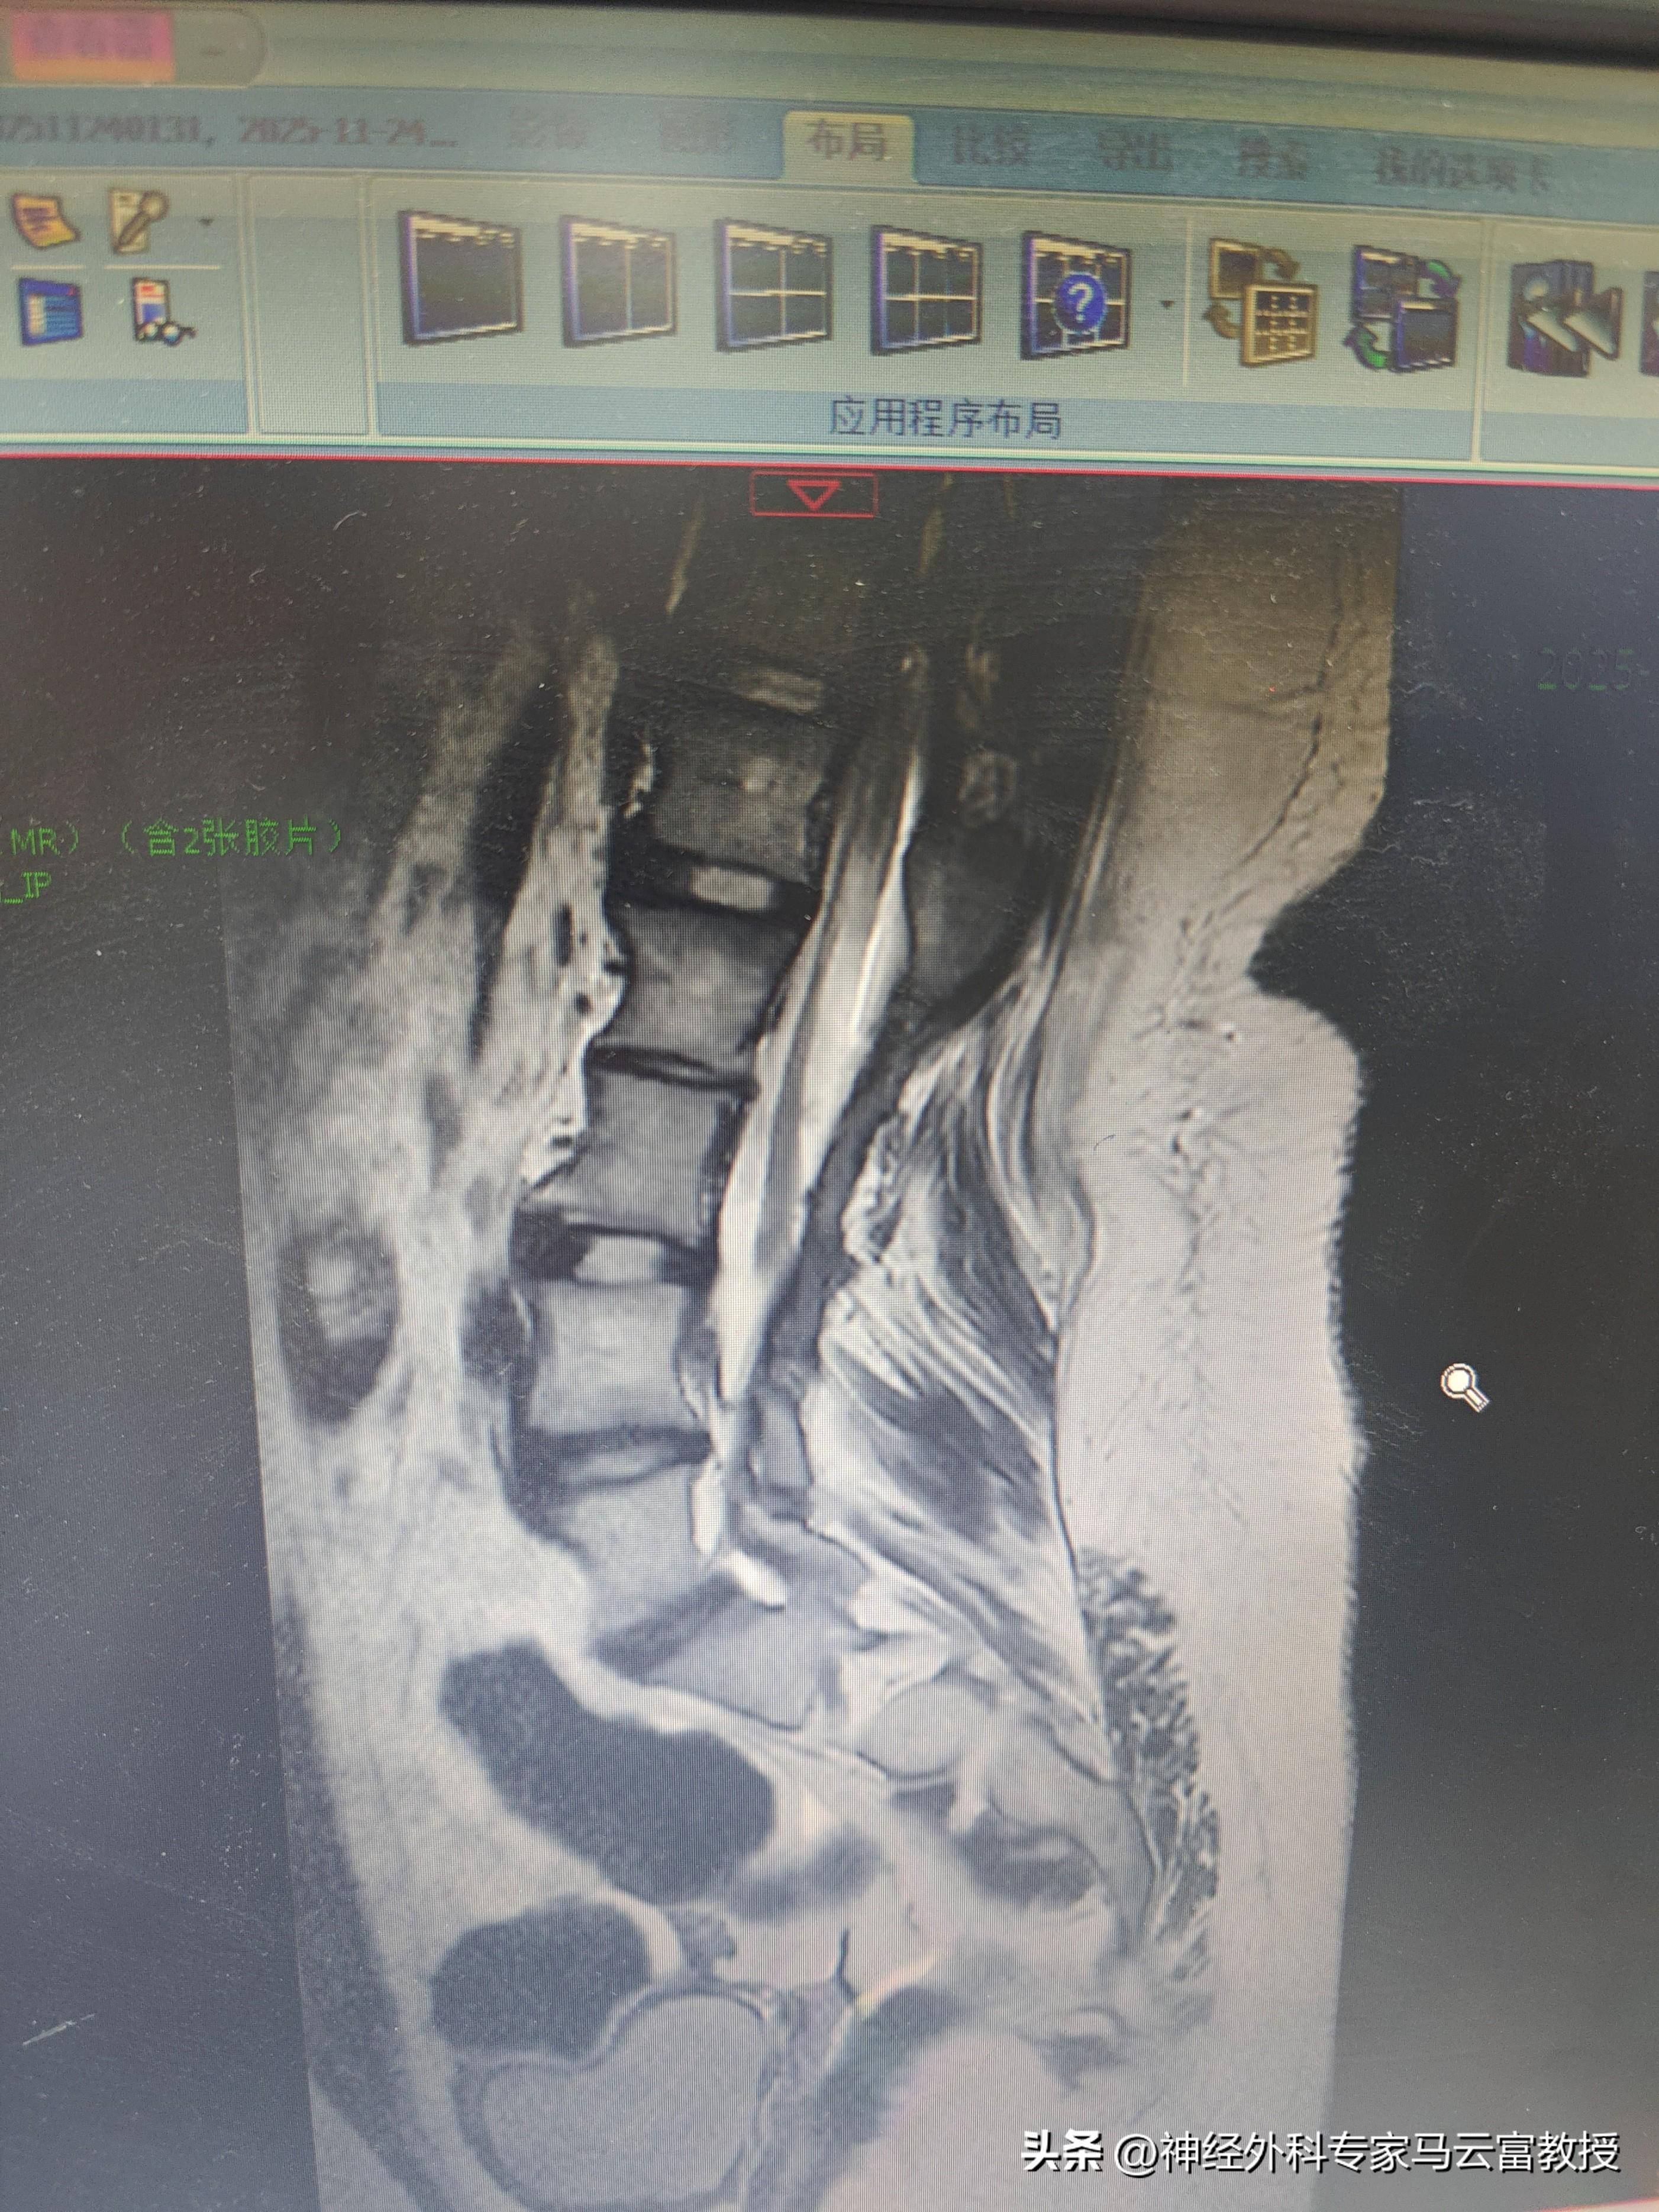

• 胸腰骶CT、腰骶MRI(核磁共振):這是評估脊柱骨骼結構和脊髓、神經根現狀的“金標準”,能清晰地顯示脊髓是否再次被牽拉,以及周圍是否存在粘連、脂肪瘤等病變。